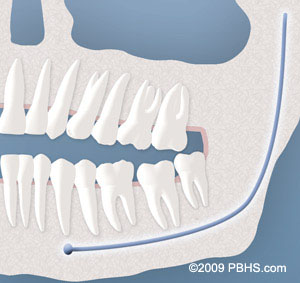

Although most people develop and grow 32 permanent adult teeth, many times their jaws are too small to accommodate the four wisdom teeth. When inadequate space prevents the teeth from erupting they are called impacted. This indicates their inability to erupt into the proper position for chewing and cleaning.

diagramof x ray and impacted wisdom teeth 1